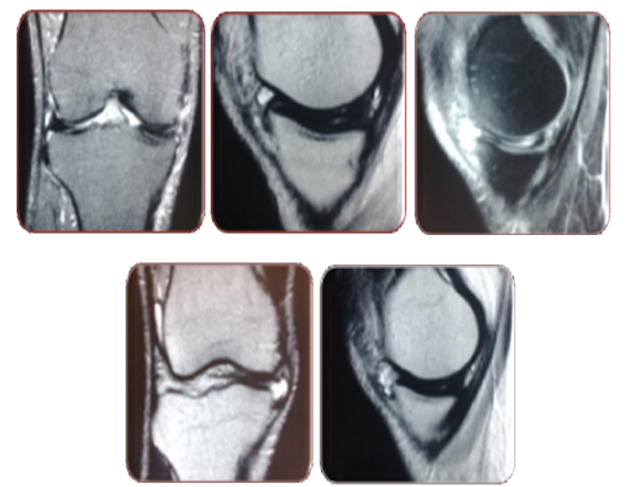

A 42 year old male consulted at arthroscopy and sports medicine institute because of right anteromedial knee pain on complete knee straightening and occasional limp and swelling on exertion. The pain was of 8 months duration, without any previous history of trauma, fall, either direct or indirect and was insidious in origin, and gradually progressive. There was occasional catching sensation especially on near complete knee extension. The pivoting activities was accompanied by pain and limp later and gradually progressed, affecting activities of daily living like prolonged standing ,sitting cross legged and squatting. The patient did notice fullness in the anteromedial region on exertion. There was no rest pain and no constitutional symptoms. Clinically, the medial joint line was tender and, Steinman II and Thessaly test were positive4 (Figure 2). He had full range of motion with pain only on terminal extension localizing medially. The lachman, pivot shift was negative. Radiographs were seemingly normal with a flat medial plateau with MRI showing a bow-tie sign persisting in all sagittal images of medial meniscus with a grade 2 signal intensity (Figure 3).

Figure 3 MRI findings (a) Coronal view confirming discoid medial meniscus, (b) Persistence of Bow-tie sign on sagittal view (c)Horizontal cleavage (d,e) Anteromedial location of cyst.

Arthroscopy confirmed an almost complete discoid medial meniscus with the free margin in contact with the ACL stump, without any evidence of abnormal attachment to ACL and medial tibial spine. The central anomalous portion of the discoid meniscus was excised arthroscopically revealing a horizontal cleavage. The cyst got decompressed once the mid segment and anterior segment junction was excised. A minimal yellow colored thick fluid was expelled during excision. Partial meniscectomy was completed leaving a well balanced peripheral rim. Post operatively the patient reported significant improvement in the VAS score from 8 to 1 (Figure 4). Physiotherapy was begun in immediate postoperative period and the recovery was good with no pain at the end of 1 week (VAS score 0) and patient did resume recreational sports after 1 month.

Figure 4 Intra-operative findings. Showing a; almost discoid medial meniscus, b; probing for tear, c; d; partial meniscectomy with balanced resected rim.